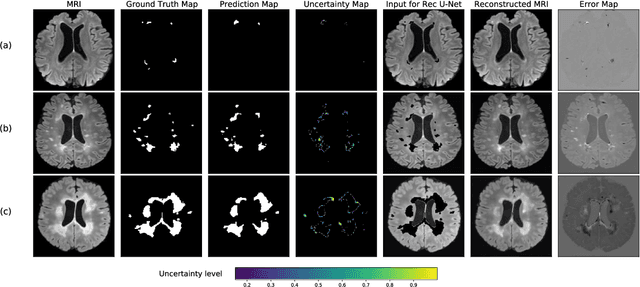

Abstract:Machine learning algorithms underpin modern diagnostic-aiding software, which has proved valuable in clinical practice, particularly in radiology. However, inaccuracies, mainly due to the limited availability of clinical samples for training these algorithms, hamper their wider applicability, acceptance, and recognition amongst clinicians. We present an analysis of state-of-the-art automatic quality control (QC) approaches that can be implemented within these algorithms to estimate the certainty of their outputs. We validated the most promising approaches on a brain image segmentation task identifying white matter hyperintensities (WMH) in magnetic resonance imaging data. WMH are a correlate of small vessel disease common in mid-to-late adulthood and are particularly challenging to segment due to their varied size, and distributional patterns. Our results show that the aggregation of uncertainty and Dice prediction were most effective in failure detection for this task. Both methods independently improved mean Dice from 0.82 to 0.84. Our work reveals how QC methods can help to detect failed segmentation cases and therefore make automatic segmentation more reliable and suitable for clinical practice.